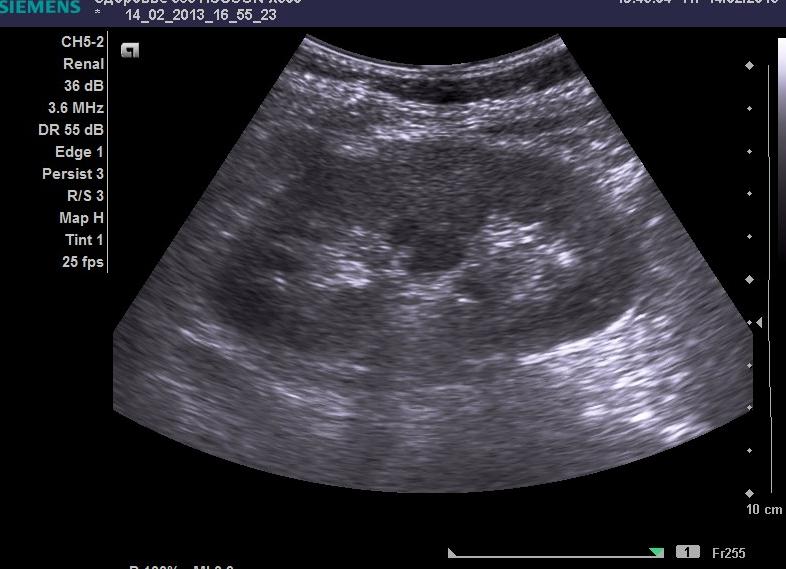

Фото:

• на чёрно-белом снимке, который доктор прикладывает к листку с описанием, хорошо заметна топография органов, их размеры. Тёмным и светлым цветом обозначены анэхогенные, гипоэхогенные и гиперэхогенные образования;

УЗИ — безопасный и информативный метод исследования почек

Фотография получается черно-белая, на ее основании доктор сможет дать описание болезни. Перед исследованием доктор выдаст рекомендации, которые помогут правильно подготовиться.